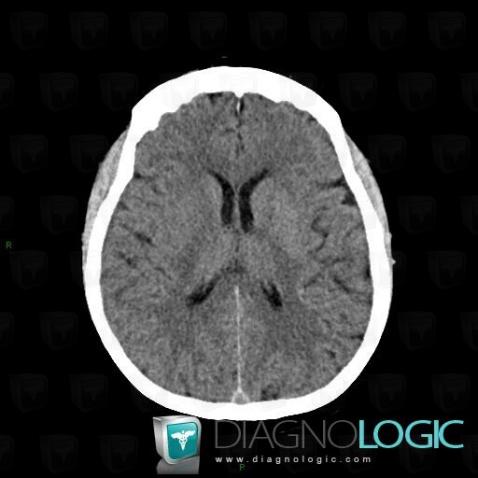

Cerebral infarction, Basal ganglia and capsule, CT

Here is the specific information in the key image above:

- Diagnosis Cerebral infarction, Location(s) Basal ganglia and capsule, with gamuts